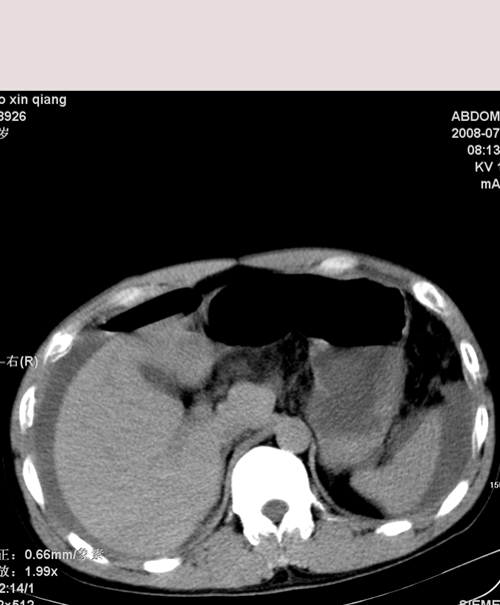

以下是引用随光逐影在2008-7-15 11:18:00的发言:[br]考虑为:1)腹部空腔脏器穿孔。2)右肾破裂并肾包膜下血肿,肾盂积血。3)腹水(血)。

以下是引用muzi888在2008-7-15 10:45:00的发言:[br]大量腹腔积液,气腹,肾皮质弧形高密度影,诊断;1 空腔脏器穿孔 2 右肾包膜下血肿

以下是引用yangyudong333在2008-7-15 12:06:00的发言:[br]考虑为:1)腹部空腔脏器穿孔。2)右肾破裂并肾包膜下血肿,肾盂积血。3)腹水(血)。